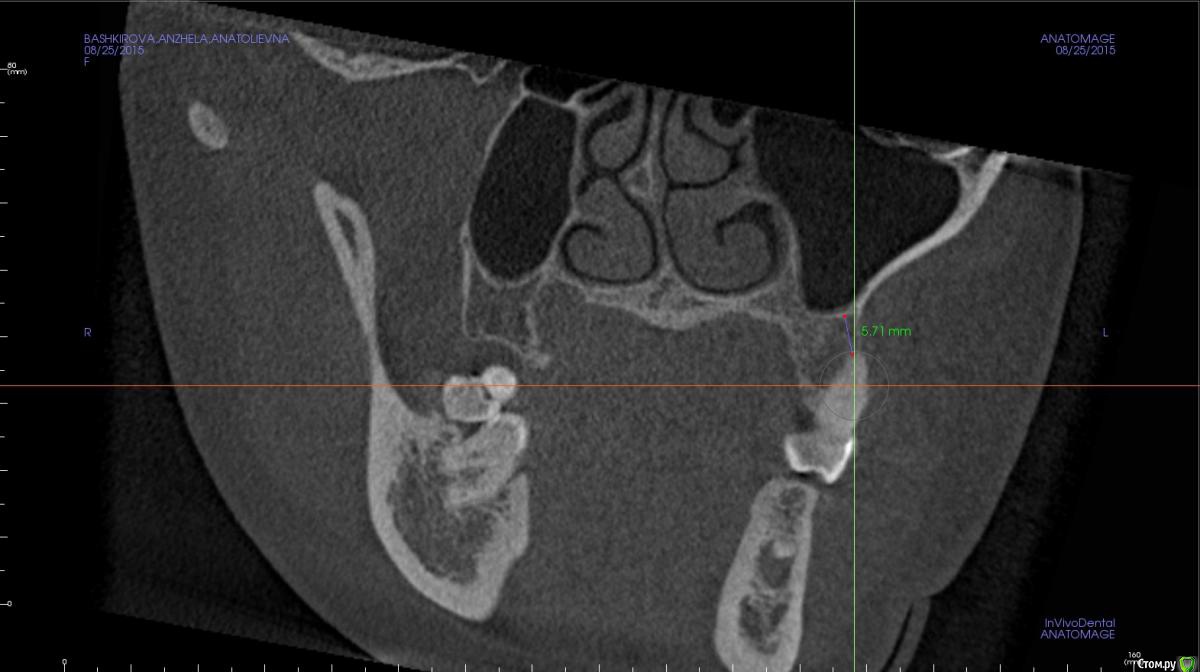

Rustam161 Опубликовано 26 августа, 2015 Поделиться Опубликовано 26 августа, 2015 Здравствуйте доктора.Необходимо произвести интрузию 26 и 27 зубов,но при осморте расположения щечных корней 26 зуба обнаружил их вестибулярное положение на снимке.В таком случае можно проводить интрузию или необходимо находить какое-то иное решение ?? Ссылка на комментарий

azerty Опубликовано 19 января, 2017 Поделиться Опубликовано 19 января, 2017 Что бы не плодить темы, подскажите коллеги,возможна ли интрузия моляров на верхней челюсти при очень близком расположении корней рядом с гайморовой пазухой?Не произойдет ли перфорация дна пазухи?Снимки прикреплю завтра,спасибо! Ссылка на комментарий

Opdihatop Опубликовано 22 января, 2017 Поделиться Опубликовано 22 января, 2017 Перфорации не будет скорее всего (особенно, если силы давать небольшие), но и интрузия идти будет очень медленно. Ссылка на комментарий

orthophil Опубликовано 6 февраля, 2017 Поделиться Опубликовано 6 февраля, 2017 Господа! О какой перфорации вообще идет речь. Моляры же не молотком вколачивать придется. А вот расстояние между верхушками и гайморовой пазухой уменьшится. Ссылка на комментарий